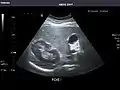

Abdominal Ultrasound (Full Exam)

STRUCTURED REPORT

(Technique: Transabdominal ultrasonography; Device: Toshiba Aplio XG)

Liver: Diffusely homogeneous and normal in echogenicity. No focal mass or contour nodularity. No intrahepatic biliary ductal dilatation.

Portal Vein: Patent main portal vein.

Gallbladder: No stones, wall thickening, or pericholecystic fluid.

Common Bile Duct: Nondilated measuring 1.3 mm at the level of the porta hepatis.

Pancreas: Visualized portions unremarkable.

Spleen: Normal in size.

Kidneys: Right and left kidneys measure 11.5 cm and 12 cm in length respectively. No hydronephrosis. Small left lower pole kidney cyst.

Ascites: None.

Aorta: Visualized portions normal in caliber, 16 x 15 mm.

IVC: Normal.

IMPRESSION:

Normal abdominal ultrasound.